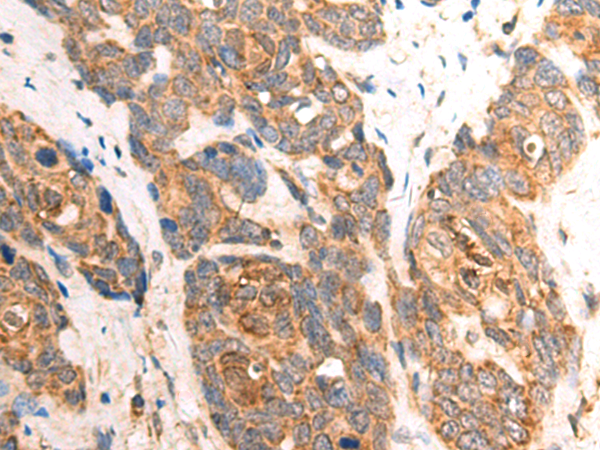

分类: 科研抗体货号: P06989别名: CPP32; SCA-1; CPP32B应用: WB,IHC反应种属: Human, Mouse, Rat